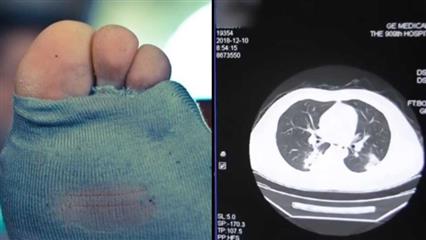

Οι μηχανές πλεξίματος καλτσών ήταν στη μόδα στην Ιαπωνία τη δεκαετία του 1990, αυτή η μόδα δείχνει να επανέρχεται